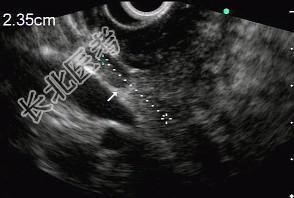

- 单项选择题男性,50岁, 上腹隐痛,食欲不振3个月。1个月来出现黄疸且进行性加深, 体重明显减轻,查体全身明显黄染, 肝未触及,深吸气时可触到肿大胆囊底部, 无触痛。化验血胆红素15mg/dl,尿检胆红素阳性图中胰腺病变可能的诊断是 ( )

E、胰腺癌